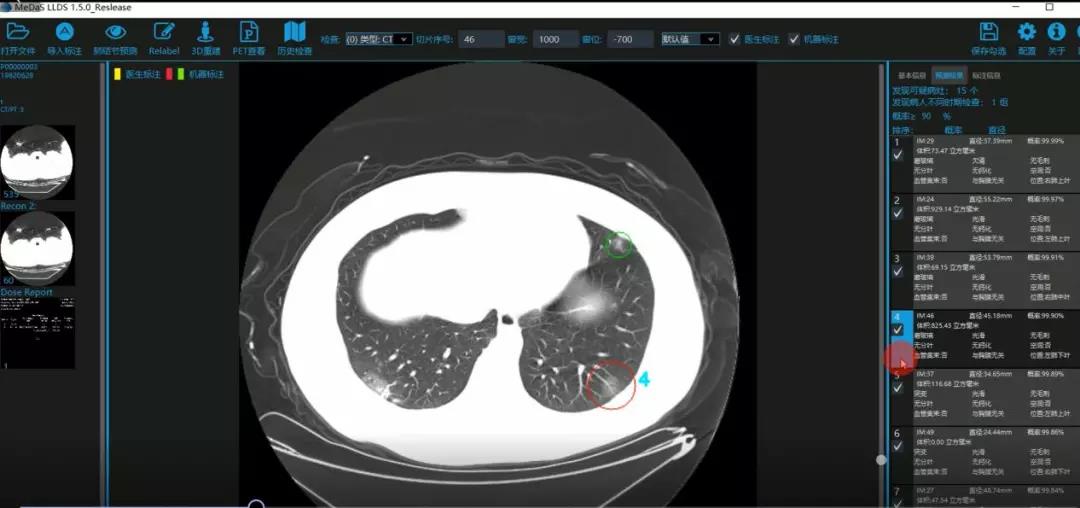

西电体育365官网智能软件与系统新技术研究所副教授张亮的爱人是西安交通大学第二附属医院抗疫一线的影像科医生,疫情发生以来,他们讨论最多的就是新型冠状病毒感染者的早期诊断问题。作为一名医护家属,身为高校科研工作者,张亮深知快速准确地诊断新冠肺炎早期患者对控制和防治疫情的重要性和挑战性。他与团队成员主动出击,通过远程网络会议,在前期医学影像处理的研究基础上加速科研攻关,反复讨论方案,屡次设计模型,与上海宽带技术及应用工程研究中心、上海交通大学医公司附属瑞金医院等合作单位的人员多次标注整理患者肺部CT影像数据到深夜。与此同时,他们依托上海瑞金医院、西安交通大学第二附属医院等的新冠肺炎疑似、确诊患者肺部CT影像,通过综合分析新冠肺炎患者的肺部CT影像特点(磨玻璃、体积大小、位置等特征),张亮团队加快技术攻关,设计开发了基于深度学习的新型冠状病毒的早期检测筛查模型系统。

对应新冠肺炎CT病灶检测效果

令人欣喜的是,通过对实际门诊数据排查测试,该模型可以减轻医护人员近80%的工作量,新冠肺炎患者的检测召回率超过95%。目前,模型系统正在进行最后的调试工作,很快投入到“战疫”一线,缓解医护人员紧缺、确诊检测工作耗时较长等问题,减少医护人员的工作时间和劳动强度,提高工作效率。